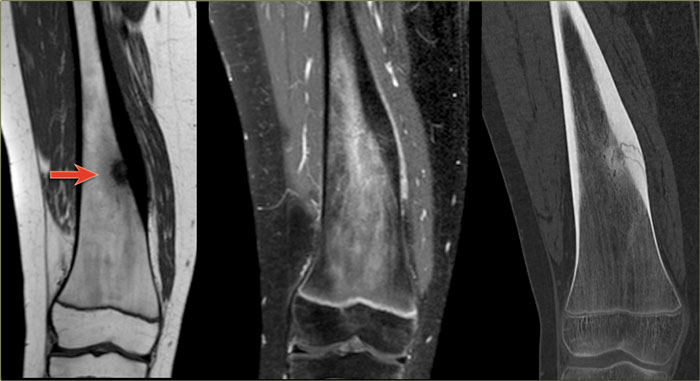

Here images of a 30-year-old male.

There is a wel-defined lytic lesion of the olecranon with several ridges and a pathologic fracture.

The differential diagnosis includes giant cell tumor and ABC.

The T2WI+FS shows fluid-levels due to sedimentation making ABC the most likely diagnosis.

Biopsy however revealed Brown tumor.